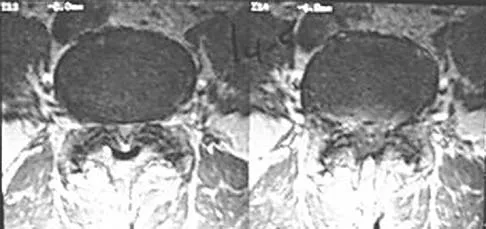

An otherwise healthy 70-year-old man has back and bilateral leg pain in an L5 distribution that is aggravated by standing more than 10 minutes or walking more than 100 feet. He has to sit to get relief. Neurologic and pulse examinations are normal. A radiograph and MRI scan are shown in Figures 4a and 4b. Treatment should consist of

Explanation

The patient has a degenerative spondylolisthesis at L4-5 with associated spinal stenosis. His symptoms are consistent with neurogenic claudication. Based on these findings, the surgical treatment of choice is decompression and posterolateral fusion. Use of instrumentation is controversial. Laminectomy alone is reserved for the patient who is frail medically. There is no role for an anterior approach or for fusion alone without decompression. Fischgrund JS, Mackay M, Herkowitz HN, et al: Degenerative lumbar spondylolisthesis with spinal stenosis: A prospective, randomized study comparing decompressive laminectomy and arthrodesis with and without spinal instrumentation. Spine 1997;22:2807-2812.